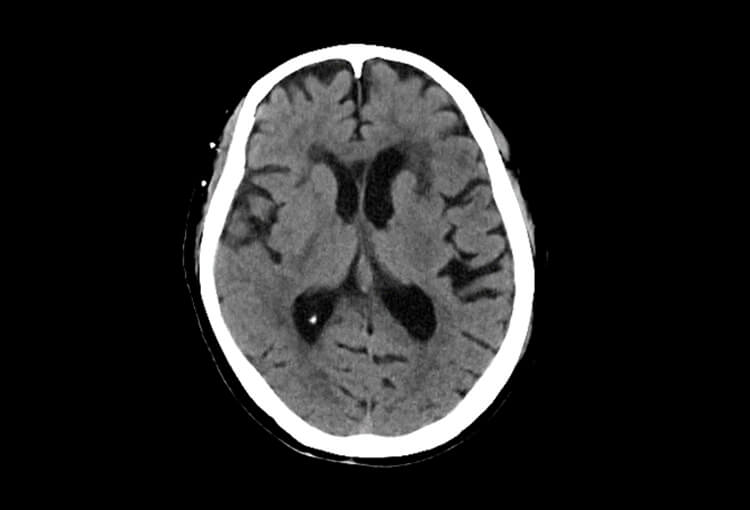

Before and After Denoising

120 kV / 30 mAs / 1mm

Before FBP (Noise 150) VS After ClariCT.AI (Noise 49) 67% Denoising